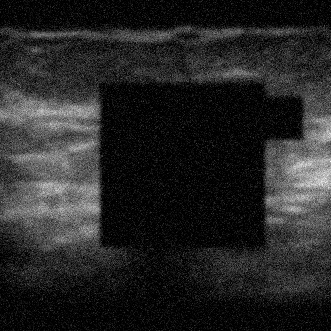

To evaluate the performance in terms of OOD detection, three different OOD test data sets were used: MNIST (test set), CorruptPOCUS and CCA. The MNIST test set consists of 10 000 images of handwritten digits [14]. The CorruptPOCUS and CCA data sets were chosen to resemble realistic OOD data, such as ultrasound images containing artefacts. The CorruptPOCUS data set resembles POCUS images of poor quality and was generated by distorting the POCUS test set by adding dark areas, blur and noise. The CCA data set contains 84 ultrasound images capturing the common carotid artery [15], i.e., non-breast US images. An example of a real POCUS image of poor quality as well as examples of the three OOD data sets can be seen in Fig. 2.